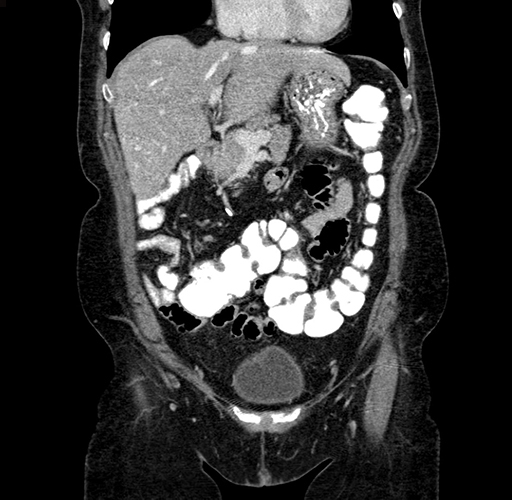

Pre-Chemo: Coronal Venous